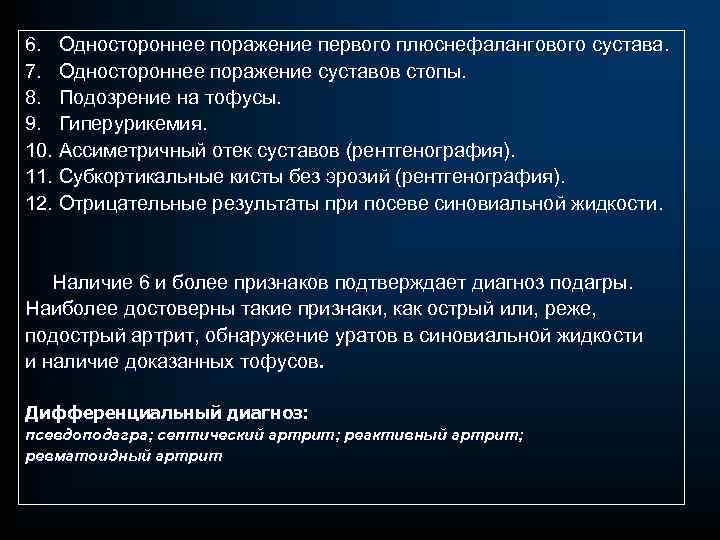

6. Одностороннее поражение первого плюснефалангового сустава. 7. Одностороннее поражение суставов стопы. 8. Подозрение на тофусы. 9. Гиперурикемия. 10. Ассиметричный отек суставов (рентгенография). 11. Субкортикальные кисты без эрозий (рентгенография). 12. Отрицательные результаты при посеве синовиальной жидкости. Наличие 6 и более признаков подтверждает диагноз подагры. Наиболее достоверны такие признаки, как острый или, реже, подострый артрит, обнаружение уратов в синовиальной жидкости и наличие доказанных тофусов. Дифференциальный диагноз: псевдоподагра; септический артрит; реактивный артрит; ревматоидный артрит

6. Одностороннее поражение первого плюснефалангового сустава. 7. Одностороннее поражение суставов стопы. 8. Подозрение на тофусы. 9. Гиперурикемия. 10. Ассиметричный отек суставов (рентгенография). 11. Субкортикальные кисты без эрозий (рентгенография). 12. Отрицательные результаты при посеве синовиальной жидкости. Наличие 6 и более признаков подтверждает диагноз подагры. Наиболее достоверны такие признаки, как острый или, реже, подострый артрит, обнаружение уратов в синовиальной жидкости и наличие доказанных тофусов. Дифференциальный диагноз: псевдоподагра; септический артрит; реактивный артрит; ревматоидный артрит